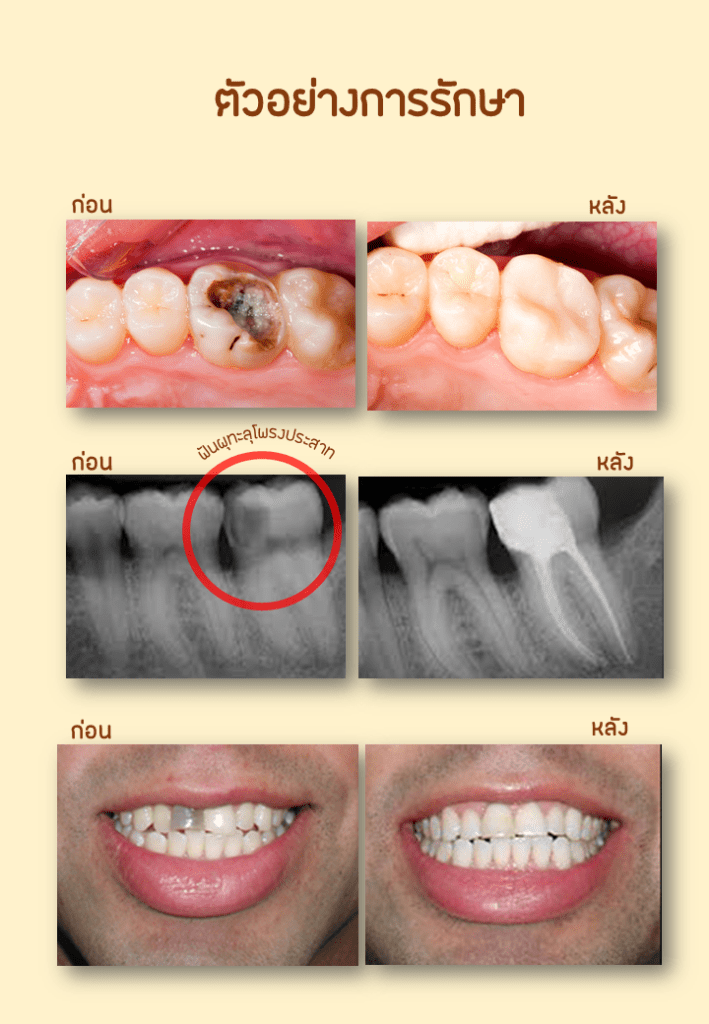

รักษารากฟันกับพี่หมี